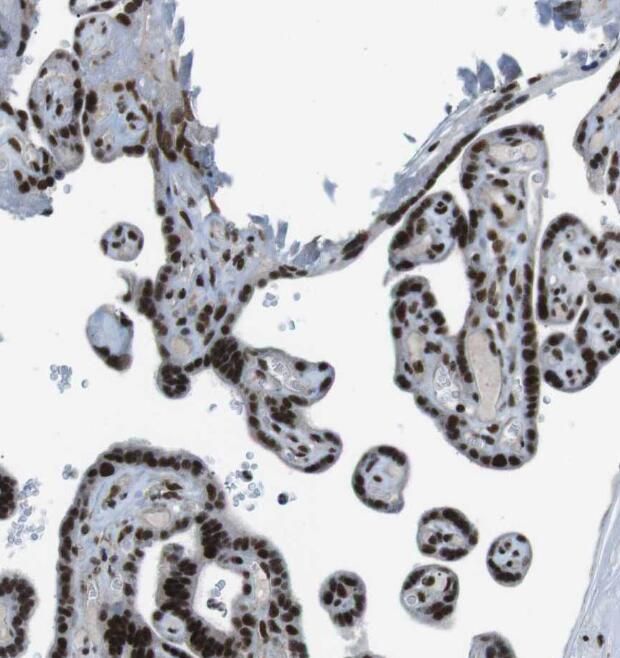

Immunohistochemistry of paraffin-embedded human placenta using FNab06830(PRR5 antibody) at dilution of 1:100